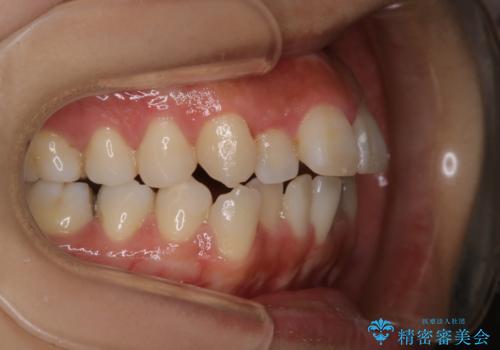

非抜歯、ワイヤーでの矯正治療。歯のがたつき、顎のズレ、出っ歯を治す。インビザラインが使えない方

- 歯のガタつき、顎のズレ、出っ歯を気にして来院された患者様です。

歯を抜きたくないとの希望であったためマウスピース治療をお勧めしましたが、

マウスピースをずっとつけていることは難しいとの事であったためワイヤー矯正治療を行うこととなりました。